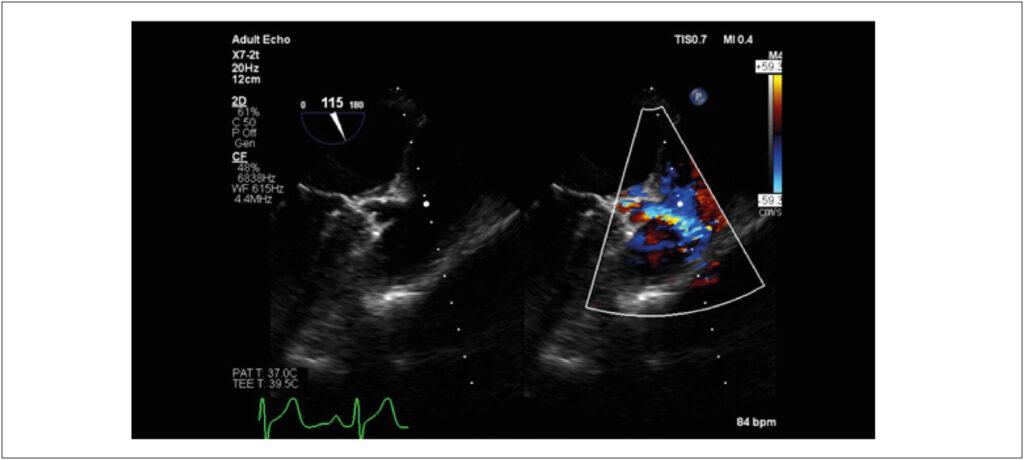

A 33-year-old female patient presented with complaints of palpitations, precordialgia, and dyspnea on exertion. Echocardiography revealed that the left coronary artery originated from the pulmonary artery with reverse flow and dilation of the right coronary artery (Figure 1, Video 1). Subsequent coronary angiography confirmed the diagnosis of anomalous left coronary artery from the pulmonary artery, also known as Bland-White-Garland syndrome (Figure 2), a rare and potentially fatal congenital pathology with an uncommon initial presentation in adults.